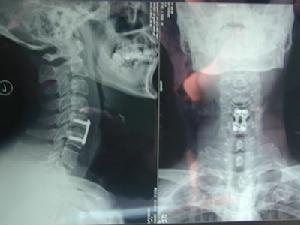

錐體骨折對於絕經後及老年性骨質疏鬆症,服用本藥能增加腸道鈣的吸收,提高血清鈣濃度,並減少錐體骨折的發病率。